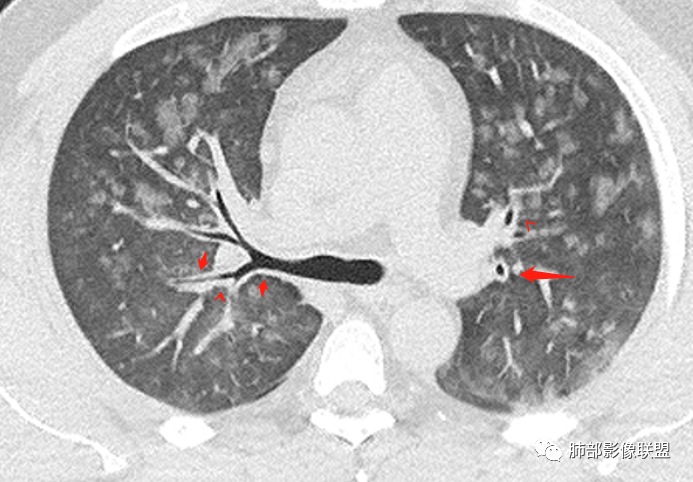

多发GGO结节,边界清,以全小叶、小叶中心为主:

GGO背景

小叶间隔增厚,无明显重力趋势

中轴间质稍增厚

细网格也明显

中轴间质增厚,小叶间隔增厚,小叶内间质增厚,部分重力作用,双侧对称,胸水,按理淋巴道回流受阻有

问题是腺泡结节如何解释?

一般吸入性病变,肺泡腔充填性病变

这是急性出血,腔充盈

时间的问题,,为什么呢,就是说,我们一般就是这样,假如这些急性的单纯的非常超急性的,那就是说,肺泡腔充填的,明显的小叶间隔增厚,那我们警惕,不对,这个是不是间质为主的,以小叶为单位间质为主的病变。

如果有出血这个还好解释,肺泡腔充盈的,还有一个弥漫性损伤也可以

一开始怀疑吸入的病变,但我看了一下很多全小叶性的,确实小叶核心区域,稍微密度偏高一点那种,我认为就是稍微一点吸收阶段都是那样的,这个我觉得还是肺泡腔充盈为主的病变,不太符合一个吸入的改变。